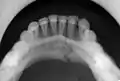

كسر الفك السفلي

كسر الفك السفلي (بالإنجليزية: Mandibular fracture) أو يعرف بأنه كسر الفك، هو كسر يحصل خلال عظام الفك.[1][2][3] يحدث هذا النوع من الكسور بسبب التعرض لإصابة وعادة ما تكون مصاحبة برضّة الوجه.

تتضمن أنواع كسر الفك السفلي الكسور في منطقة الارتفاق الذقني ورأد الفك وزاوية الفك وعنق اللقمة.